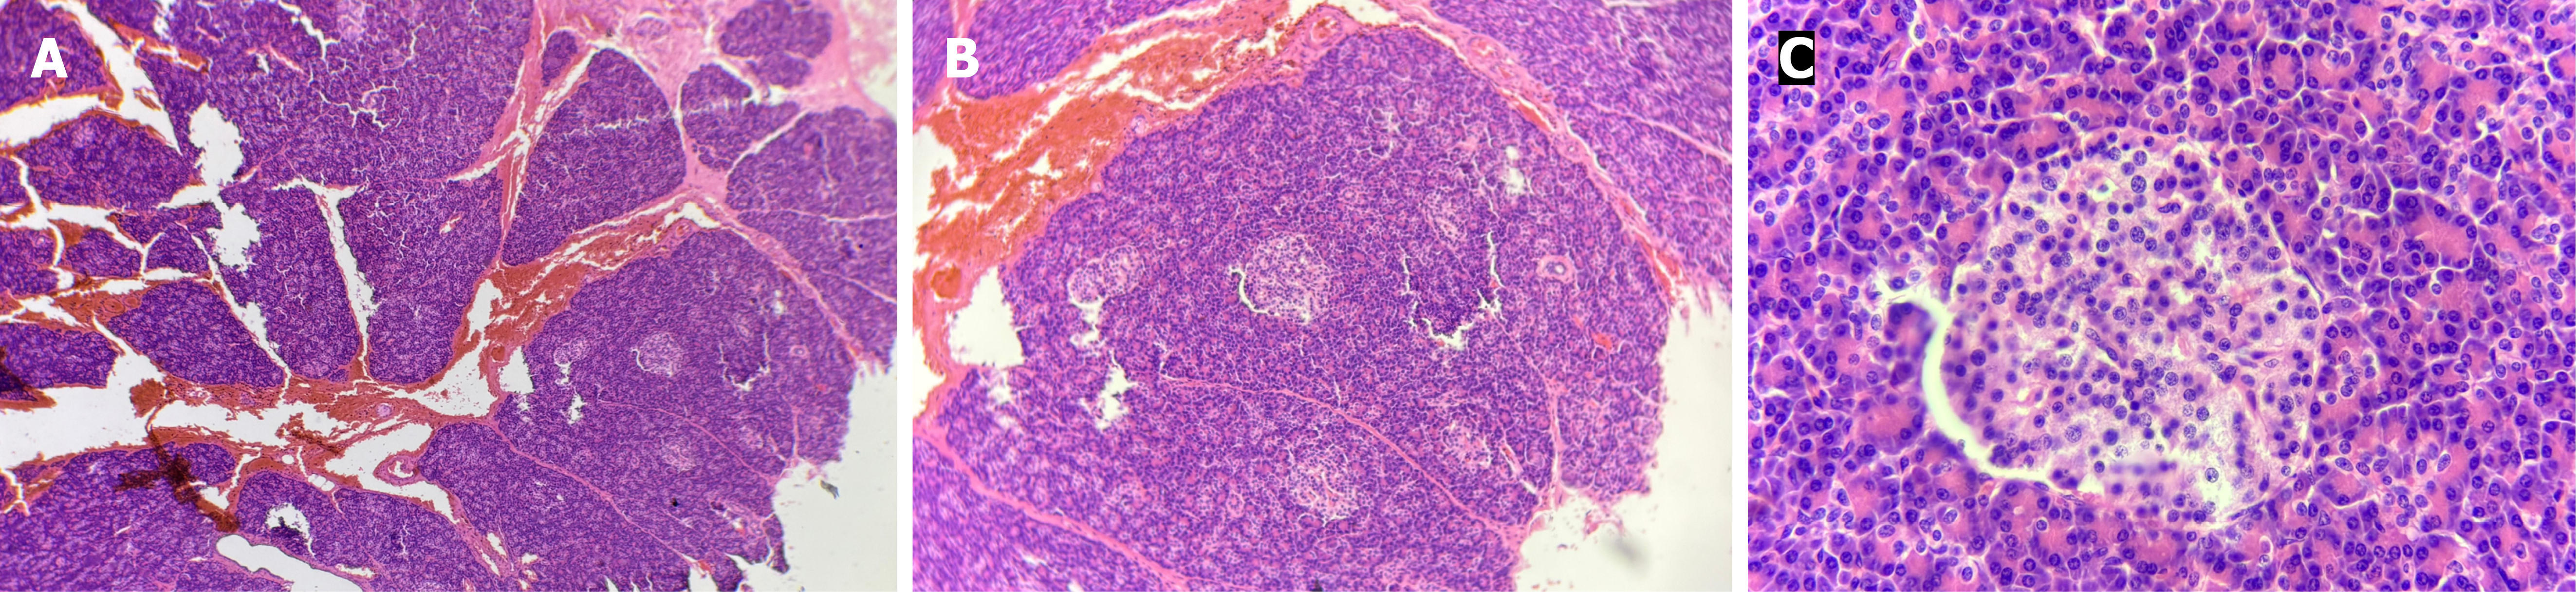

Figure 4 Histopathological images of the pancreatic specimen stained using hematoxylin & eosin stain.

A: Pancreatic architecture with lobules and acini at 100 × magnification; B: Increased numbers of pancreatic islets noted at 400 × magnification; C: Enlarged islet noted at 1000 × magnification.